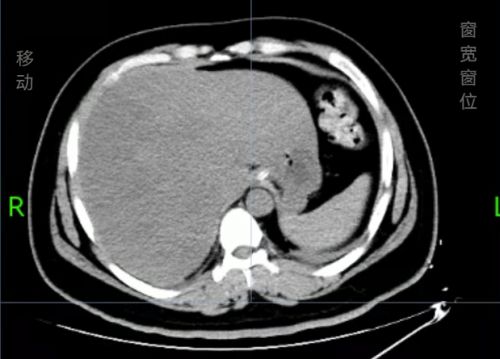

治疗后积气消失。